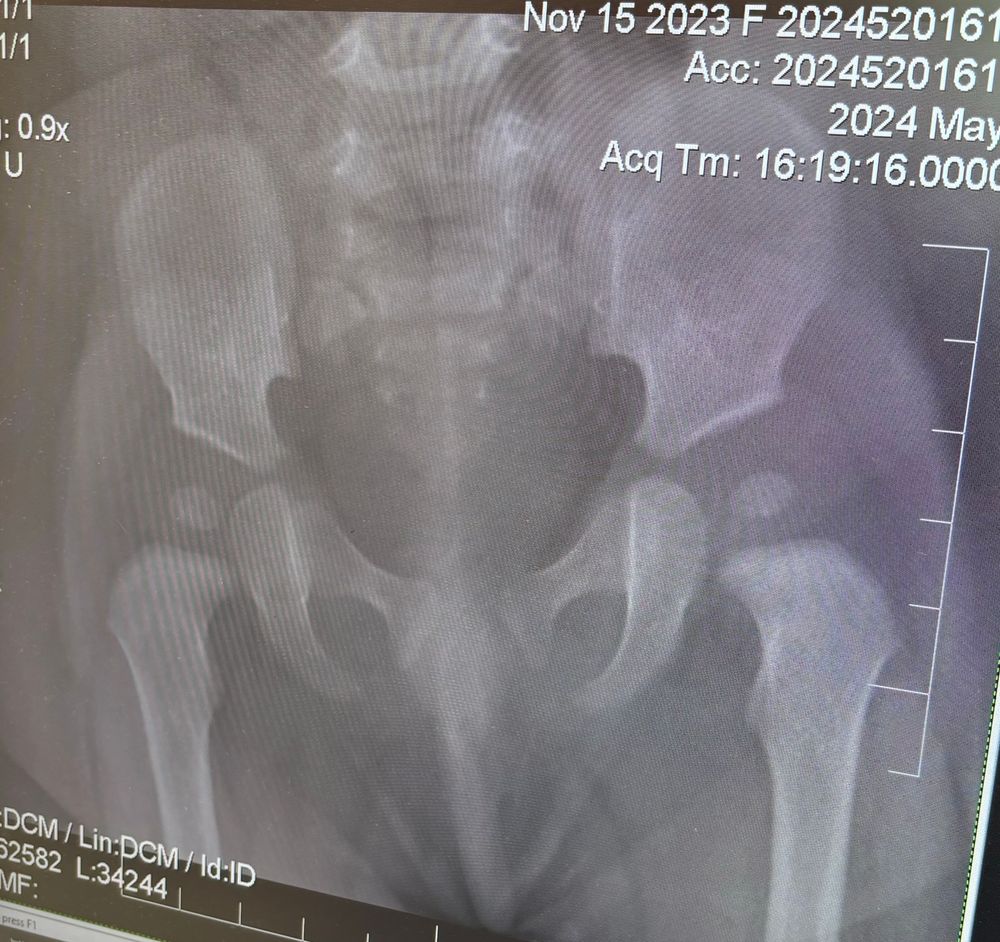

Нам один врач ставить дисплазию , говорит ставить гипс .Другой врач , советует шину «Вклинского», говорит дисплазии нет , есть тонус .Кому верить ? У кого была похожее ситуация? Ребенок в 6 месяцев , ползает и встает на ноги у опоры , сама , мы не помогали , делали 2 курса массажа , парафин , электрофарез с кальцием и пьем кальций

Я не врач,но ноги у 6 месячного ребенка,явно напряжены,или вы их держали?

Вероника, держала , со всей силой )))

На пером снимке , она еще умудрилась повернутся